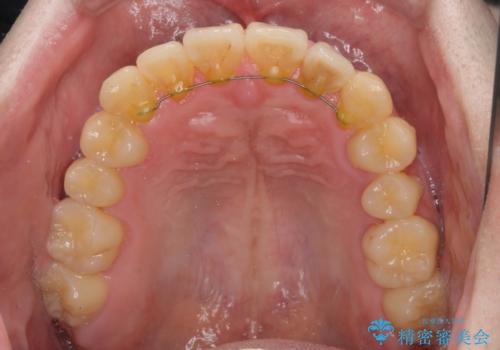

前歯のクロスバイト インビザラインによる矯正治療

- 上下のクロスバイトと前歯のデコボコを気にして来院された患者様です。

インビザラインを用い、IPR(歯と歯の間を削る)と歯列全体を拡大させることで、歯並びを整えていくこととしました。

上下ともに歯列全体を後方に移動させるため、上下の親知らずを抜歯することとしました。

奥に位置していた上の前歯が下の前歯を乗り越える際、奥歯でものを咬むことができず、辛い時期が続きました。